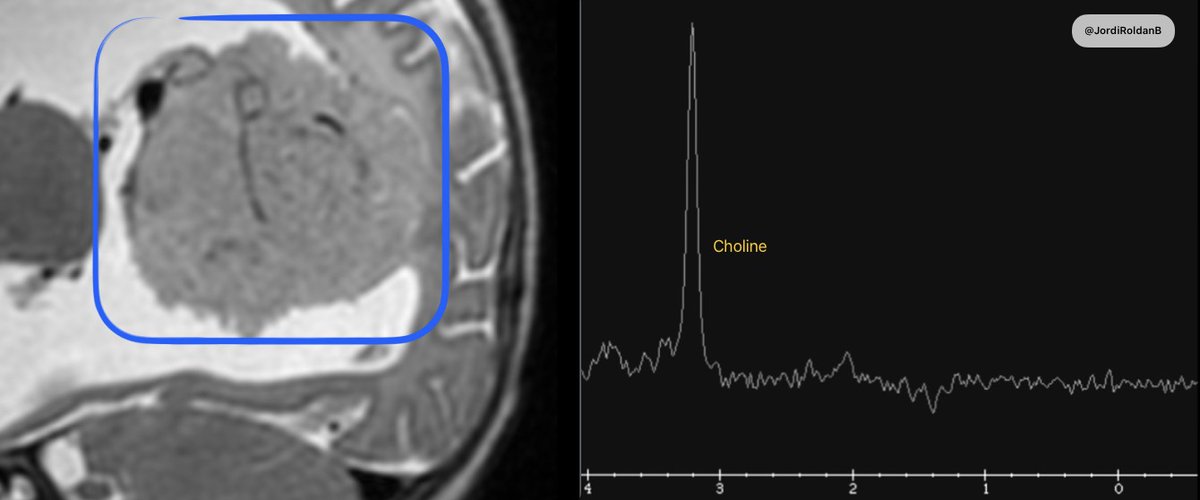

@JordiRoldanB

4 months

Context: intraventricular pediatric mass 🧠 One peak to rule them all: choline. No NAA. No creatine. 📉 Neuron-free profile. 🎯 Highly suggestive of choroid plexus tumor. #MRI #PediatricNeuro